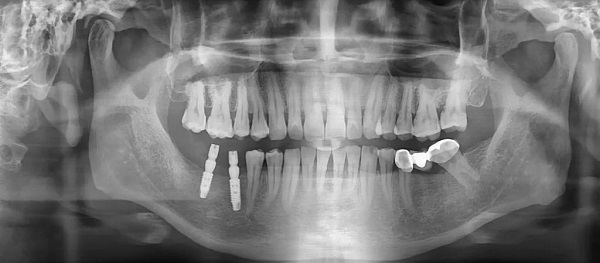

Chụp X quang toàn cảnh răng (chụp Panorama răng)

Đây là phương pháp chụp X quang được sử dụng để kiểm tra toàn bộ khoang miệng. Bằng cách sử dụng kỹ thuật chụp cắt lớp vi tính, nha sĩ có thể thấy rõ răng và mô xương. Trong quá trình chụp, bệnh nhân sẽ được bảo vệ bằng áo chì và cố định trên máy để thu được hình ảnh sắc nét của răng và xương hàm dưới.

Hình ảnh Panorama răng là một công nghệ chụp X quang cho thấy rõ về xương hàm trên và dưới, các thành phần lân cận như khớp thái dương hàm, xoang mũi. Kỹ thuật này cũng cho phép bác sĩ nhìn thấy toàn bộ hai cung răng trên một phim giúp chẩn đoán nhiều loại bệnh lý răng miệng như răng mọc lệch, răng mọc ngầm, u nang, áp xe và tổn thương xương hàm.

Ưu điểm của kỹ thuật Panorama răng là thời gian chụp nhanh, hình ảnh chất lượng cao, an toàn và phù hợp với mọi đối tượng, bao gồm cả trẻ em – nhóm khách hàng khó chụp X quang bằng các phương pháp truyền thống. Tuy nhiên, điểm trừ của phương pháp này là không phát hiện được những vấn đề như lỗ sâu răng, gãy xương, nhiễm trùng,…